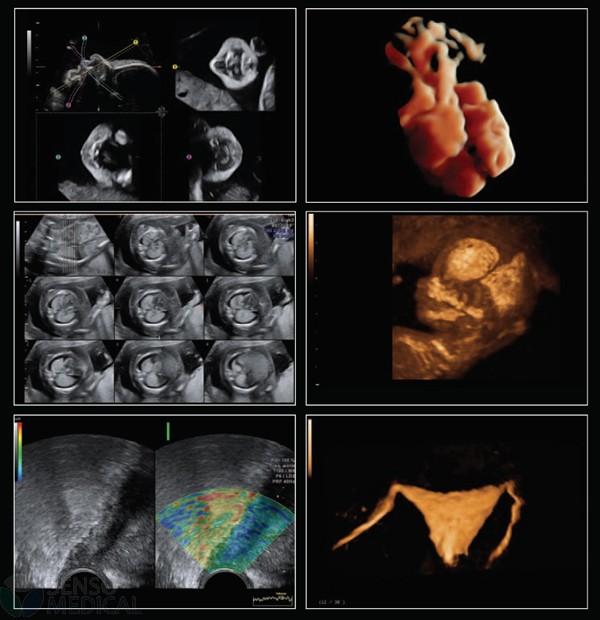

Ultrasonograf GE Voluson E8 Expert wersja oprogramowania BT13 (UISApp 13.0.6.254) 4D HDLive –

System Voluson E8 Expert to unikalne rozwiązanie w zakresie diagnostyki chorób kobiecych oferujące wysoką jakość obrazowania w trybach 2D i 3D/4D oraz uproszczone procedury usprawniające przepływ pracy i zapewniające najwyższą jakość badań. Więcej szczegółów, mniej wysiłku!

Oprócz najnowocześniejszych opcji obrazowania w usg 2D 3D 4D oraz opcji dopplerowskich posiada także funkcję ELASTOGRAFII.